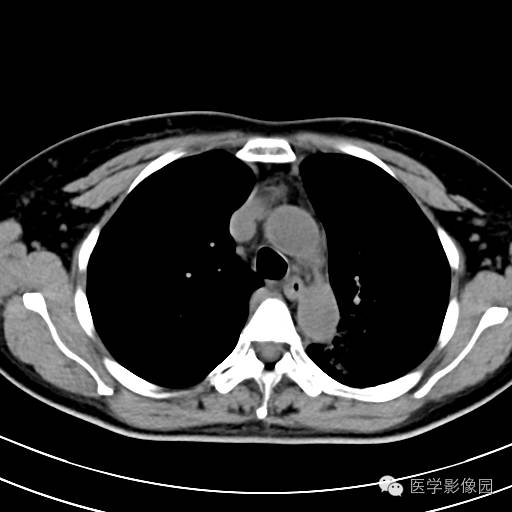

肺叶实变性支气管肺泡癌1例CT影像表现